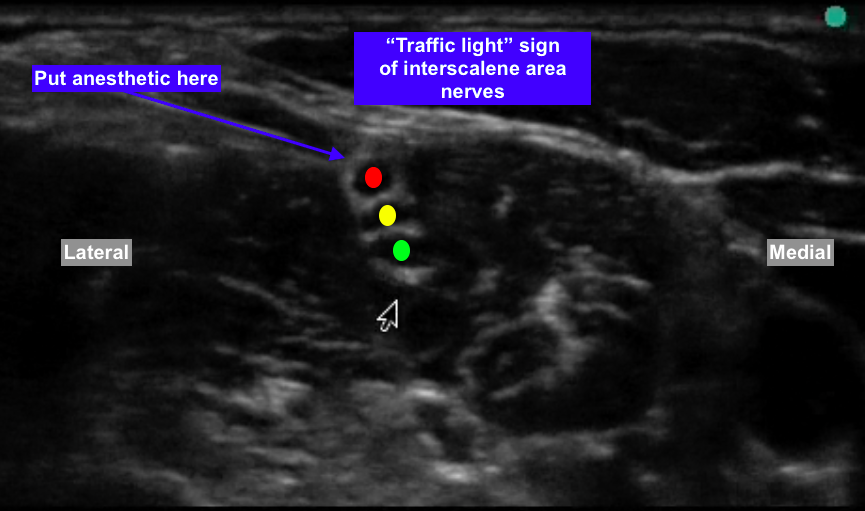

So when you are looking at 3-5 black circles in the interscalene groove, how do you differentiate which ones are C5, C6, C7 vs. multiples coming off the same root? For example how do we know in the picture below that we are not looking at C5, C6, C6, C7 (or any other anatomical variant).

Or do you simply inject tangential to the posterior border of the cluster of 3 "stoplights"?

Or do you inject tangential to the superior border of the cluster? In my mind this is incorrect because superior deposition I think will likely lead to anterior spread and increased phrenic nerve blockade.

So when you are looking at 3-5 black circles in the interscalene groove, how do you differentiate which ones are C5, C6, C7 vs. multiples coming off the same root? For example how do we know in the picture below that we are not looking at C5, C6, C6, C7 (or any other anatomical variant).

Or do you simply inject tangential to the posterior border of the cluster of 3 "stoplights"?

Or do you inject tangential to the superior border of the cluster? In my mind this is incorrect because superior deposition I think will likely lead to anterior spread and increased phrenic nerve blockade.